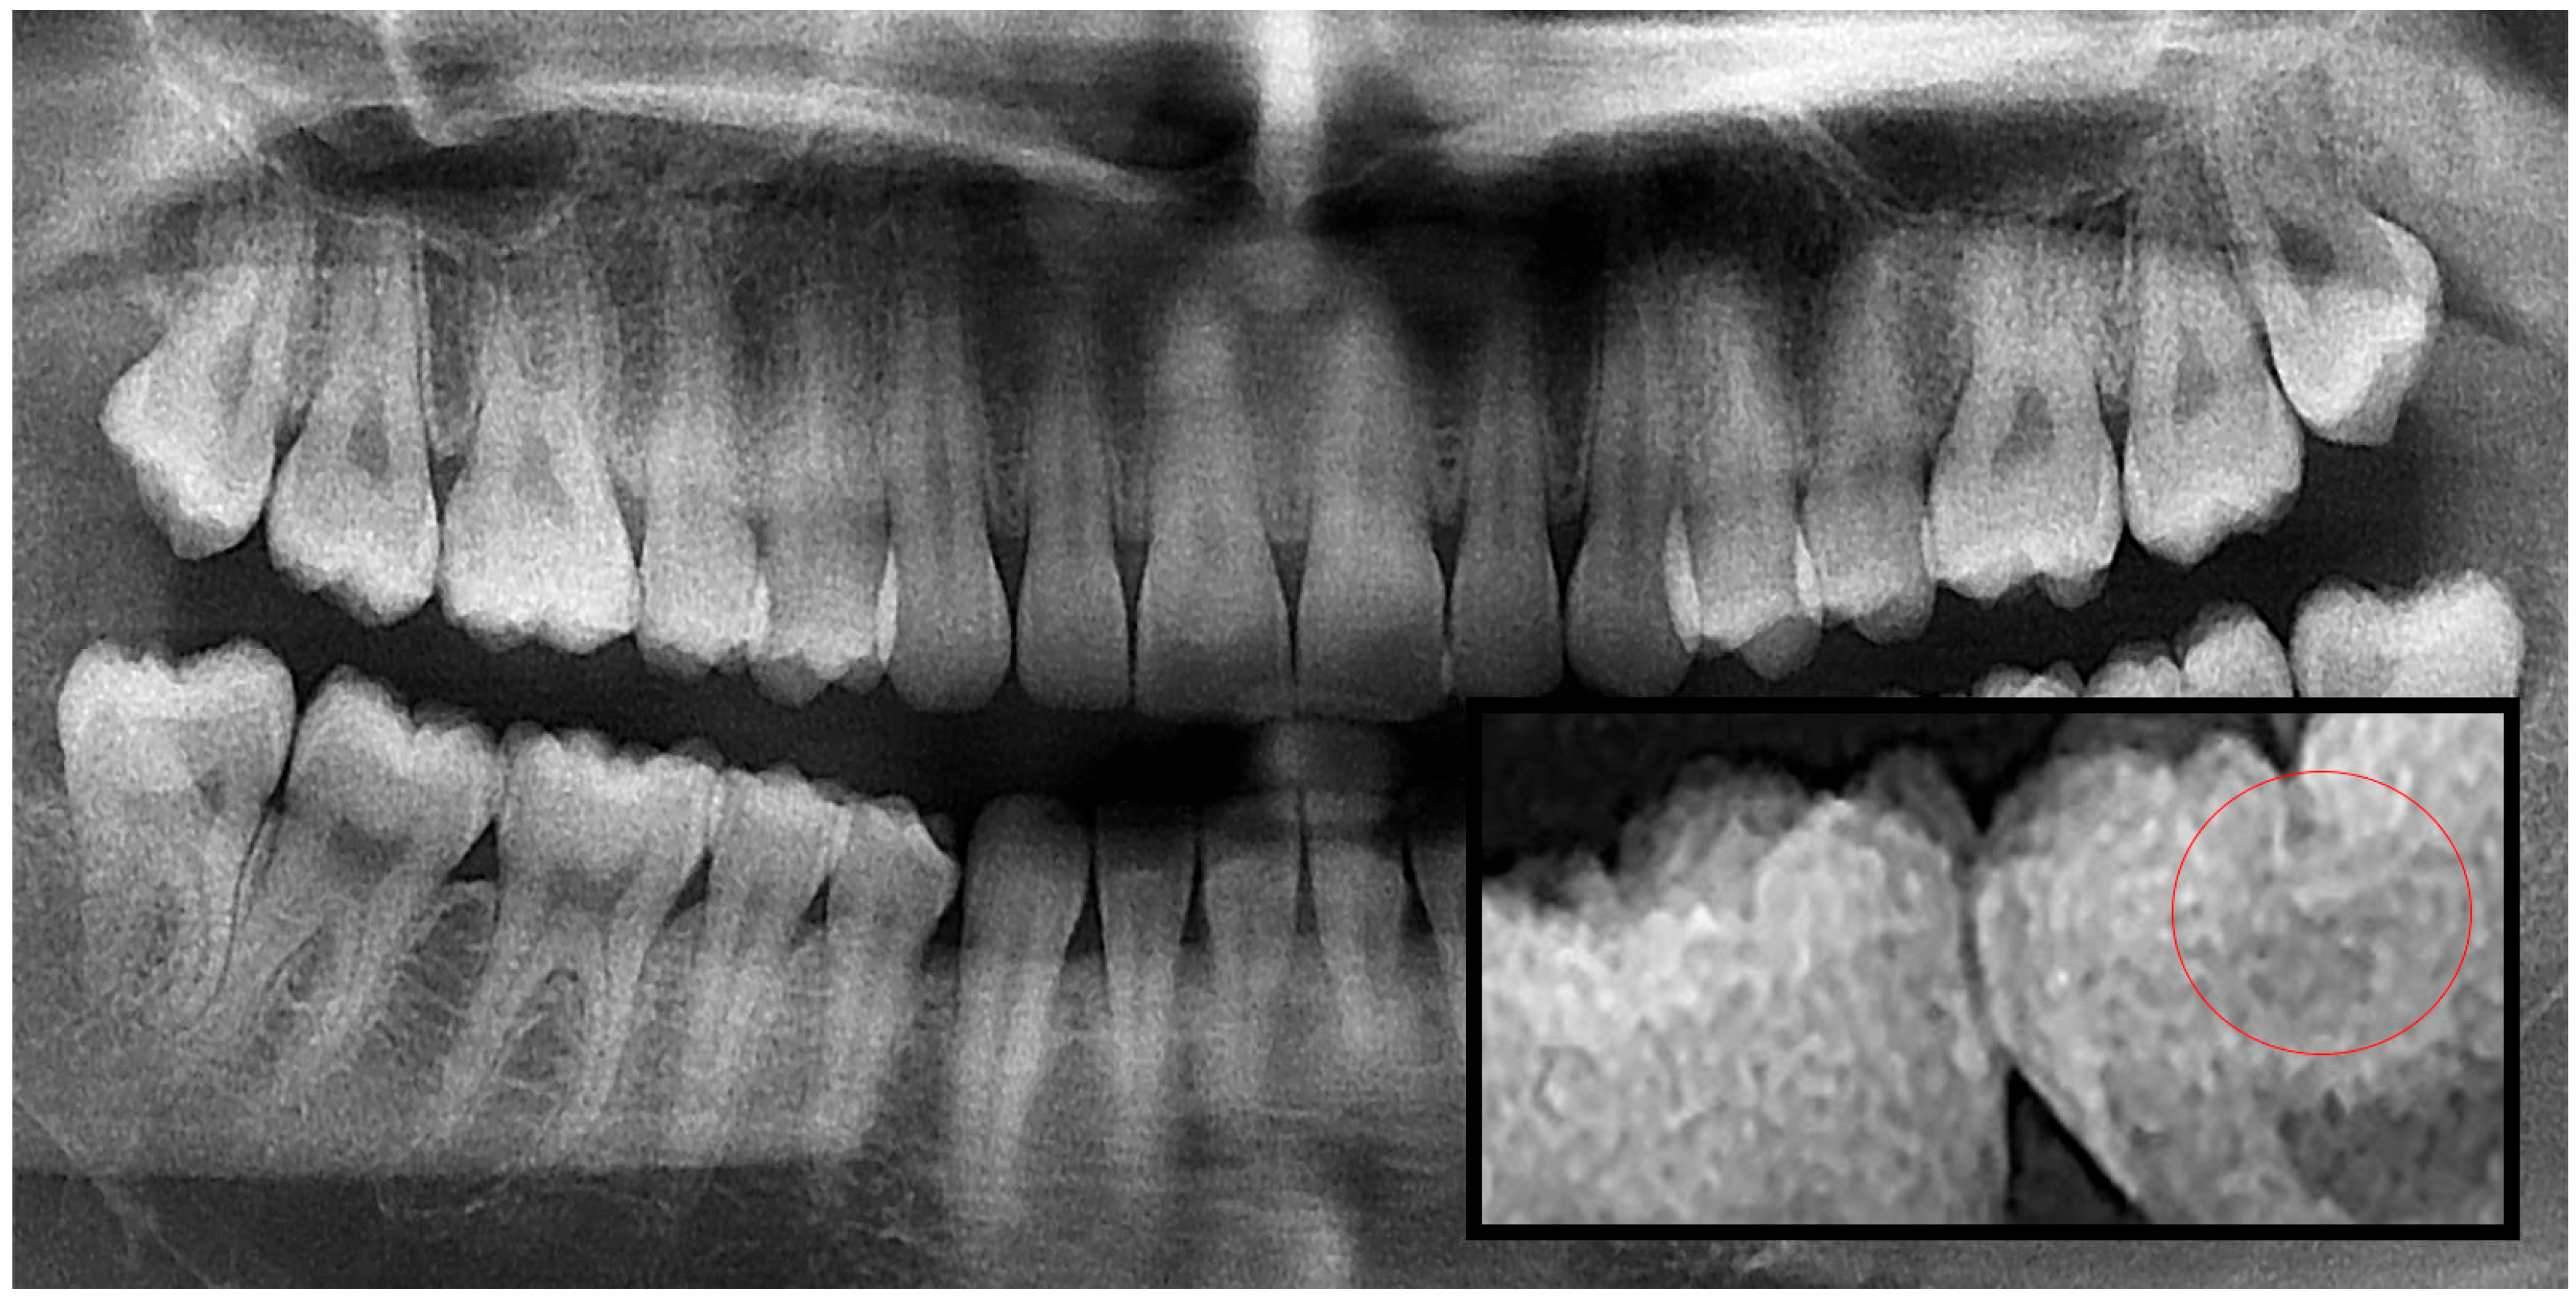

2.1. Evaluation and Categorization of Panoramic Radiographs

2.2. Image Processing and Segmentation